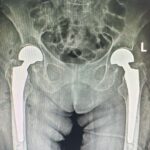

Premieră medicală în județul Sibiu: artroplastie bilaterală de șold realizată într-un singur timp operator, la SCJUS DESCARCĂ DOCUMENT